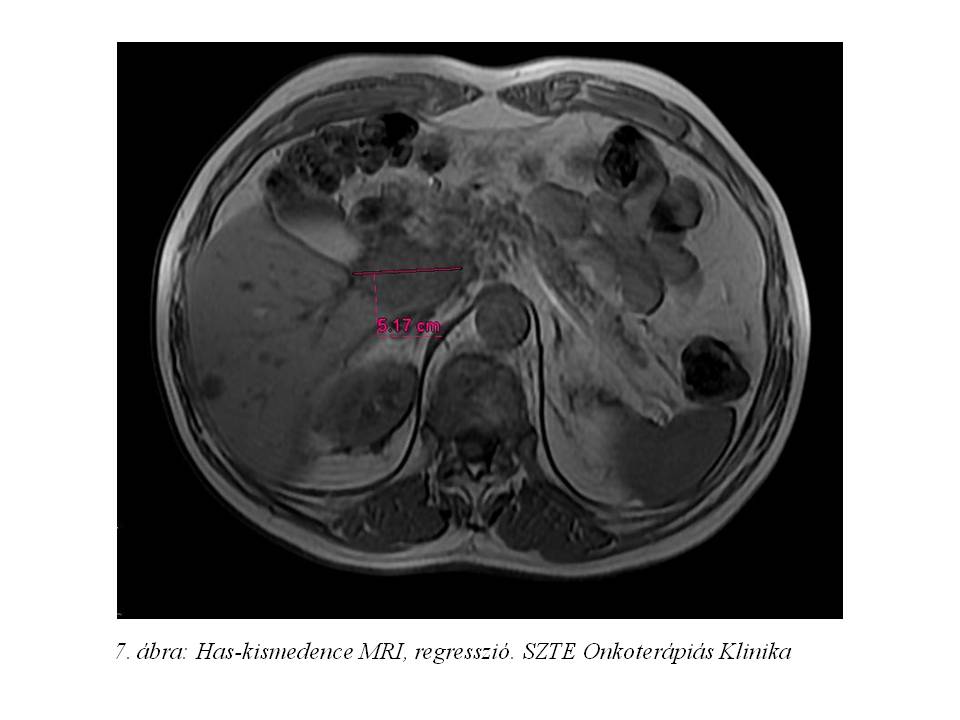

A progresszió miatt lanreotid kezelését egyedi méltányossági kérelem alapján sunitinib kezeléssel egészítettük ki. A kombinált terápia mellett az ismert mellékhatások, úm. vérnyomás emelkedés és –kiugrás, ill. HFS jelentkezett. Kezelésünk hatására a has-kismedence MRI-n (7. ábra) a primer tumor tekintetében regresszió és nekrózis, a májáttétek tekintetében pedig a kontrasztanyag halmozási dinamika olyan jellegű megváltozása került detektálásra, mely az áttétek vaszkularizációjának csökkenésére jellemző.